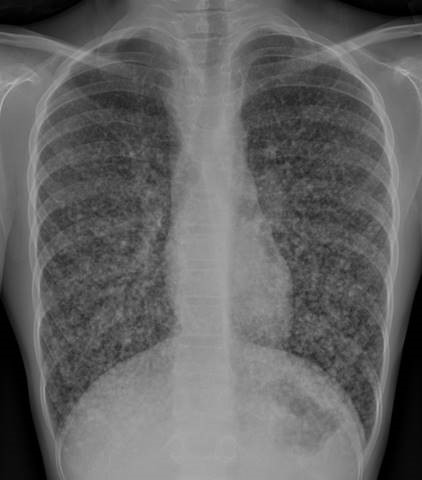

- CXR

Chest Xray: “Diffuse miliary pulmonary nodules with questionable mediastinal lymph nodes is favored to represent a granulomatous process like sarcoidosis. A healed granulomatous infection is another consideration. Chest CT is recommended.”

Chest CT Read: “There are innumerable tiny nodules scattered throughout the lungs with a miliary pattern. Appears to have progressed since the radiograph of 2015. There is no confluent airspace consolidation. There is no pleural effusion or pneumothorax. The heart size is normal. There is mild widening of the right paratracheal stripe and mild fullness of the left hilum, which may be a reflection of lymphadenopathy.

IMPRESSION: Diffuse miliary pulmonary nodules with questionable mediastinal lymph nodes is favored to represent a granulomatous process like sarcoidosis.”